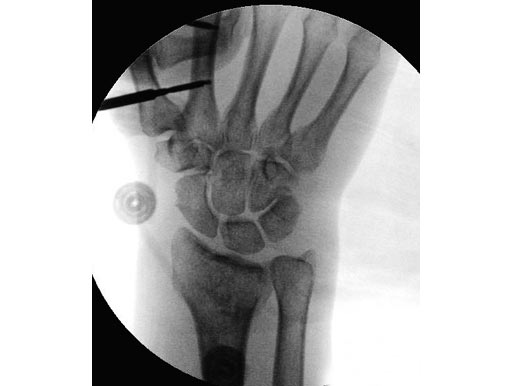

54-year-old female with 23-C3 fracture after fall

External fixator due to severe soft-tissue trauma. Palmar plate 1 week later. .